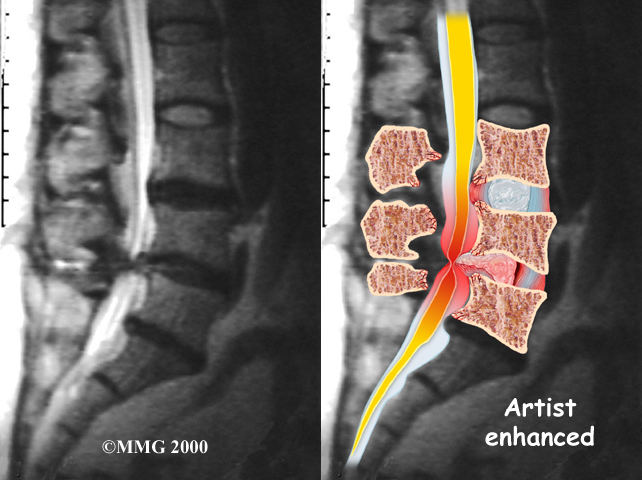

Disc herniation: Spinal stenosis can occur when an intervertebral disc in the low back herniates (ruptures). Normally, the shock-absorbing disc is able to handle the downward pressure of gravity and the strain from daily activities. However, if the pressure on the disc is too strong, such as landing from a fall in a sitting position, the nucleus inside the disc may rupture through the outer annulus and squeeze out of the disc. This is called a disc herniation. If an intervertebral disc herniates straight backward, it can press against the nerves in the spinal canal, causing symptoms of spinal stenosis.

Disc Herniation

The best way to see the effects and extent of lumbar spinal stenosis is with a magnetic resonance imaging (MRI) scan. The MRI machine uses magnetic waves rather than X-rays to show the soft tissues of the body. This test gives a clear picture of the spinal canal and whether the nerves inside are being squeezed. This machine creates pictures that look like slices of the area your doctor is interested in. The test does not require dye or a needle.